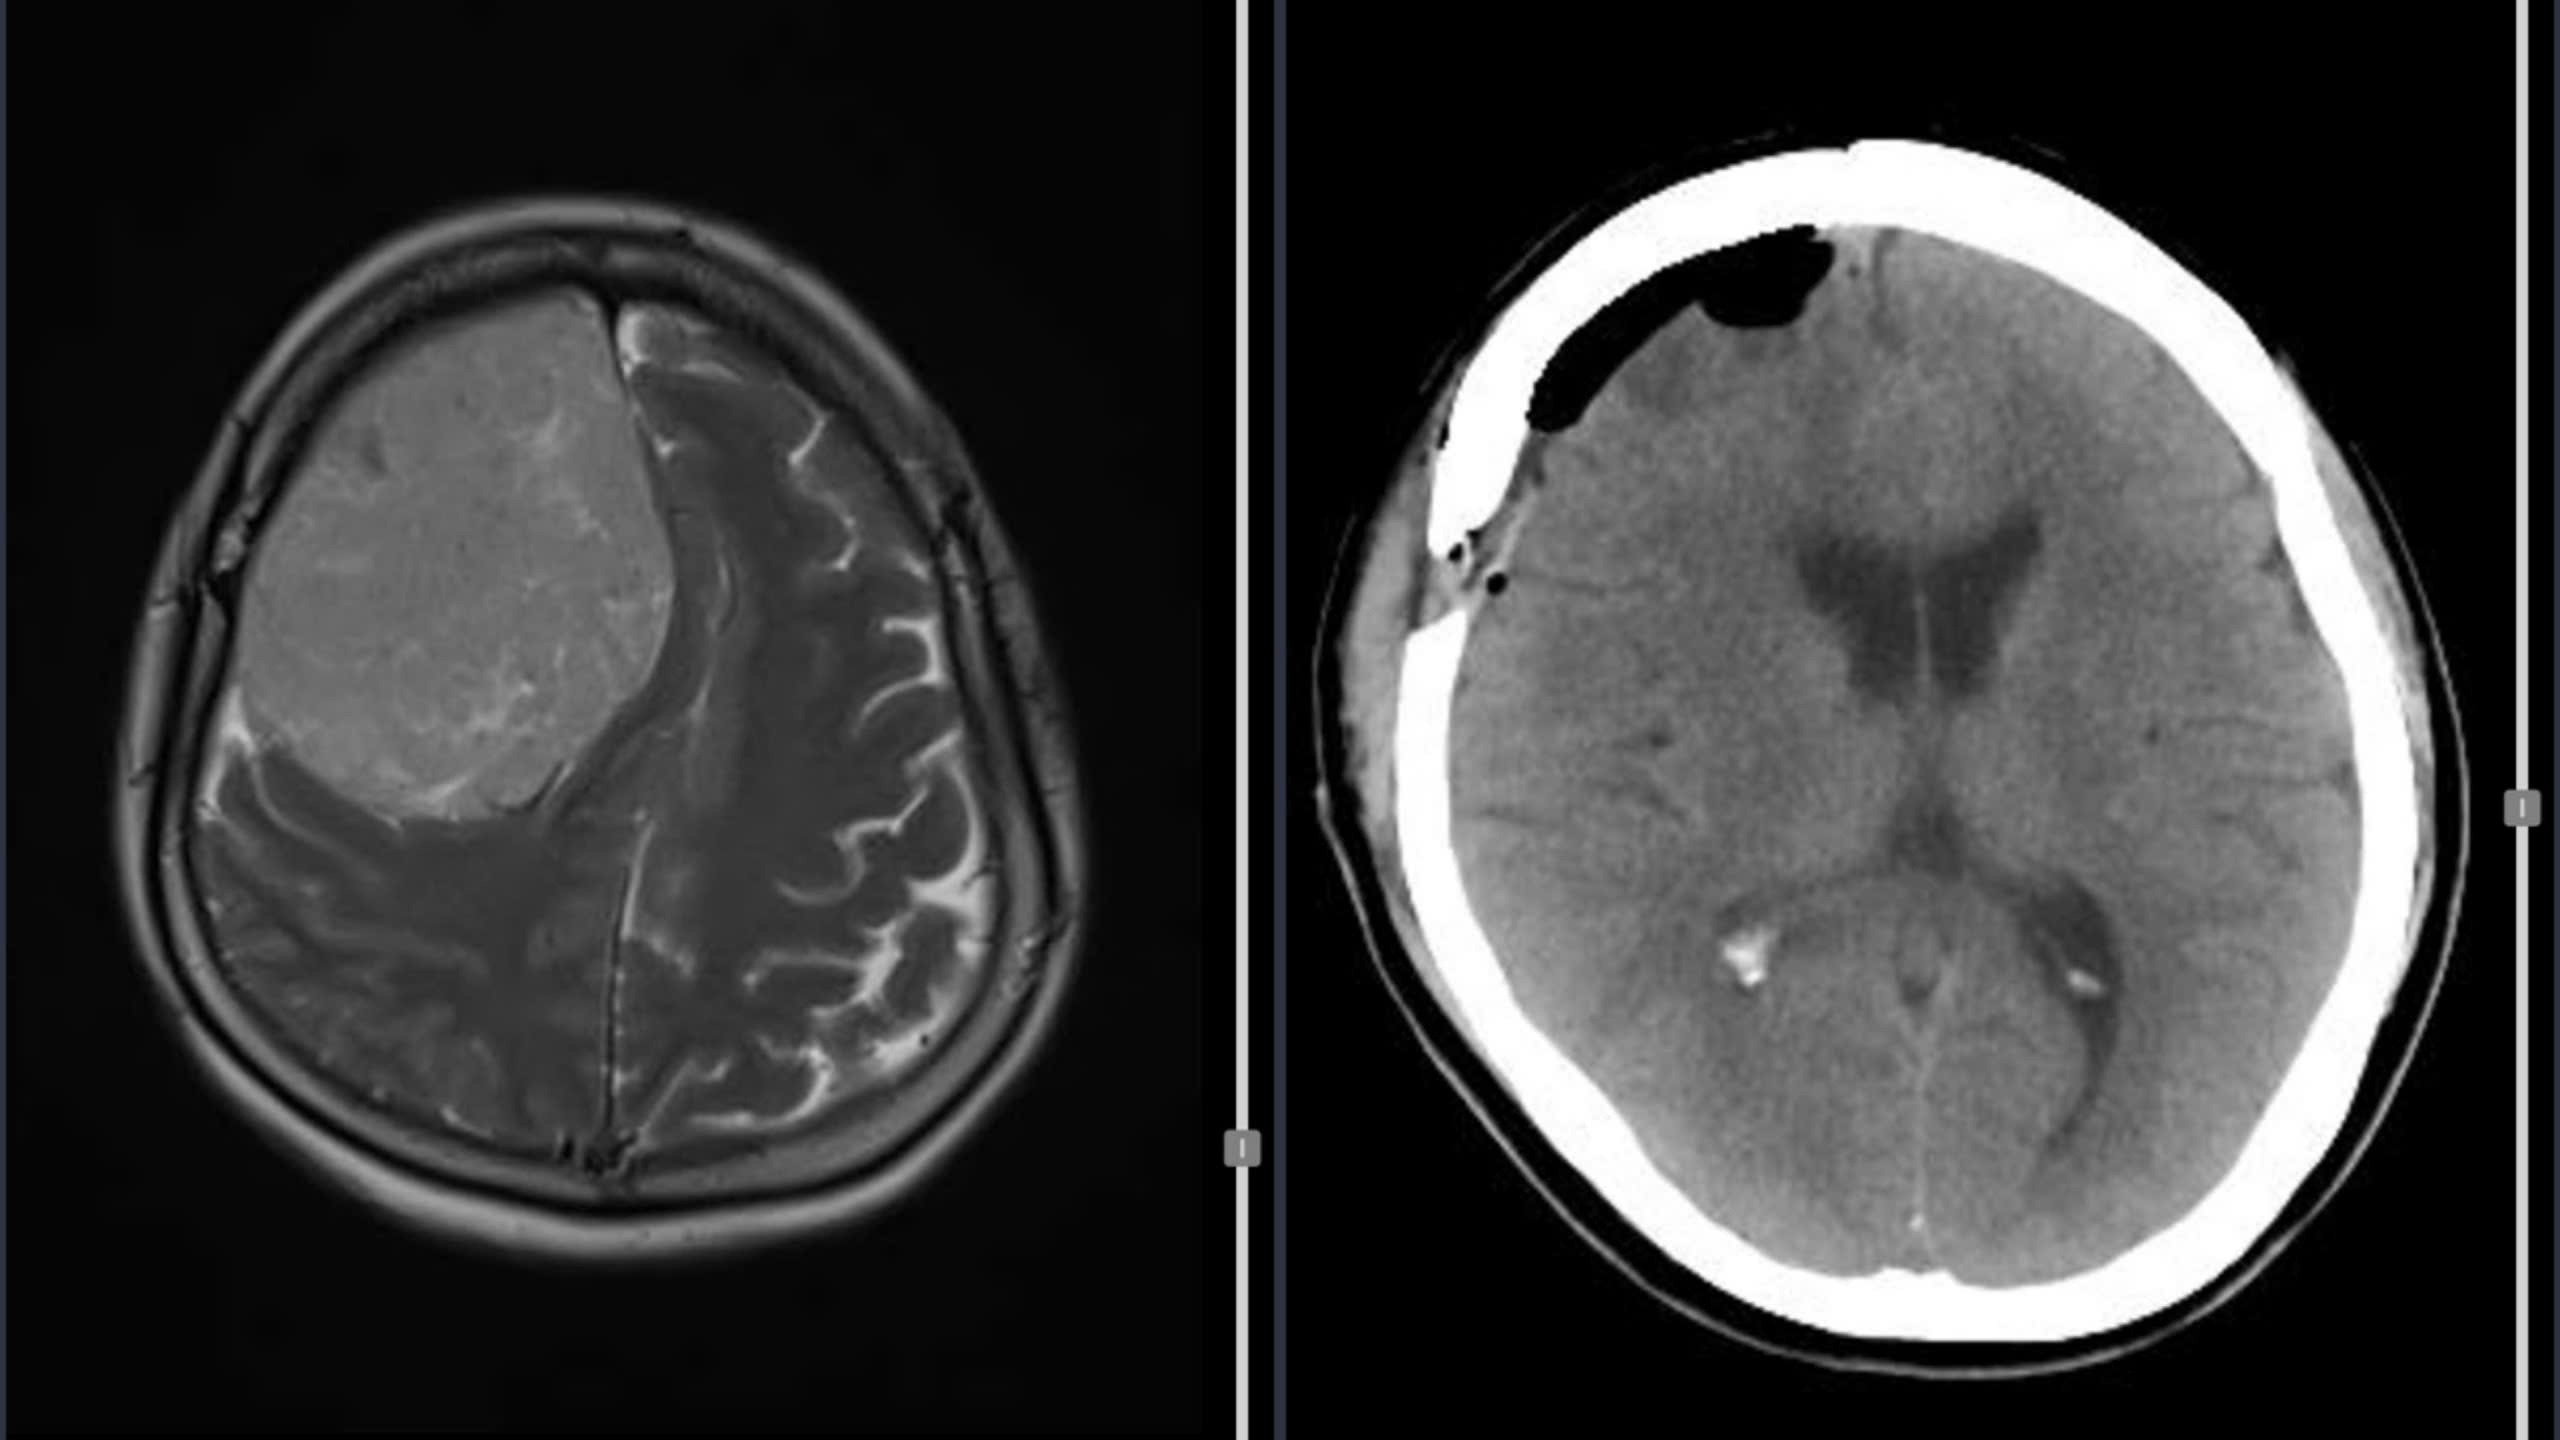

Hình ảnh MRI của bệnh nhân trước mổ (trái), CT sau mổ

Trước đó, bệnh nhân K. nhập viện với triệu chứng đau đầu dữ dội, nôn ói và yếu nửa người trái kéo dài khoảng 6 tháng. Hình ảnh chụp MRI cho thấy khối u chèn ép nhiều lên các cấu trúc não của bán cầu phải. Sau khi được hội chẩn chuyên khoa và chuẩn bị kỹ lưỡng, ngày 27.10, ê kíp phẫu thuật đã tiến hành mổ lấy trọn khối u. Sau mổ 4 giờ, bệnh nhân tỉnh táo, cử động tứ chi bình thường, hình ảnh CT kiểm tra cho thấy khối u đã được lấy hết hoàn toàn. Bệnh nhân hồi phục tốt và được xuất viện sau 5 ngày điều trị.